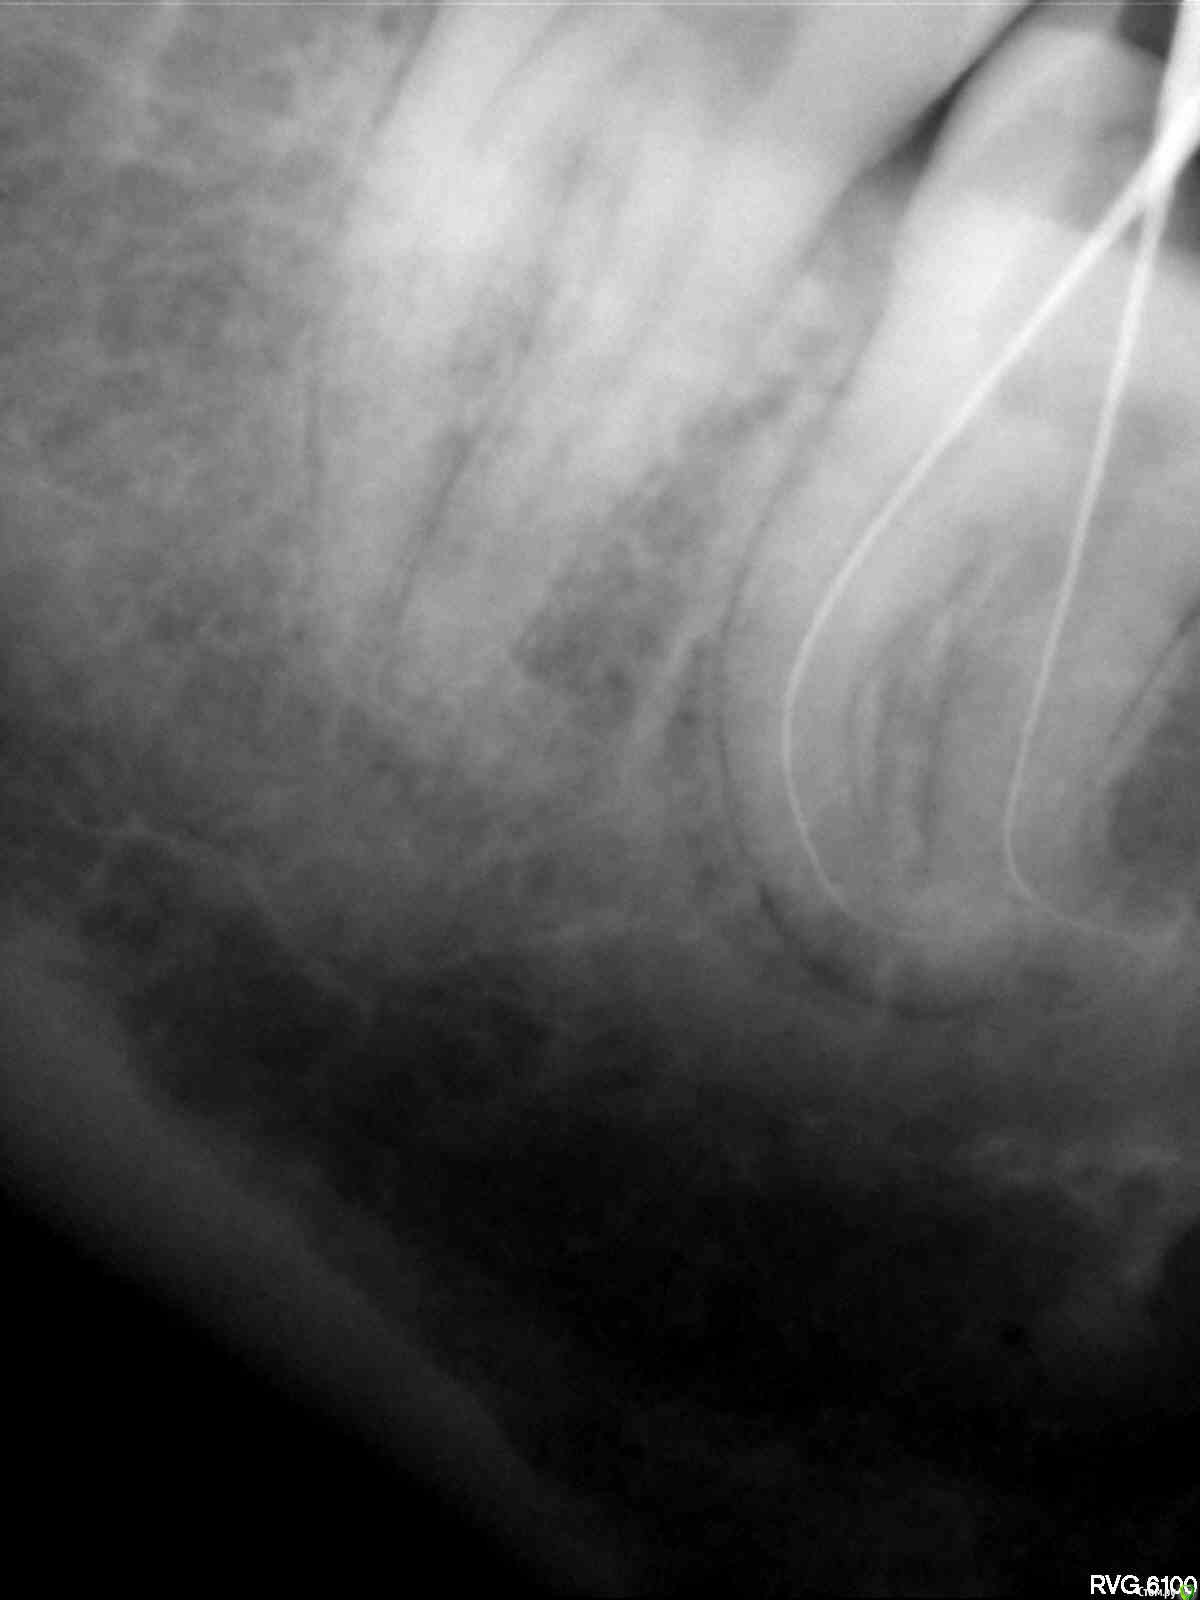

Витторио Орлионе Опубликовано 24 июня, 2015 Поделиться Опубликовано 24 июня, 2015 Уважаемые коллеги, очень нужен ваш мудрый совет. Пациентка обратилась в клинику 23.06 с жалобами на пульсирующие боли в области нижней челюсти слева. На окклюзионной поверхности зуба 3.8 глубокая кариозная полость не сообщающаяся с полостью зуба. Зондирование болезненно, температурная проба положительная, перкуссия слабо болезненна. Пациентка хотела сохранить зуб. Поэтому анестезия, некрэктомия, раскрытие и формирование полости, обработка ручными и mtwo файлами, мыл гипохлоритом. Итог: патенси нет, обломок инструмента, пульпевит №3, септопак. Явка 25.06. Если лечить то:Сообщать ли пациентке об обломке?Какую тактику выбрать (вести на каласепте или отмыть и запломбировать, стоит ли пытаться достать)?Чем пломбировать каналы (гуттаперча или резорцин)? Если удалять то?Как обосновать пациентке смену лечения на удаление?Разделять корни или нет? Ссылка на комментарий

Витторио Орлионе Опубликовано 24 июня, 2015 Автор Поделиться Опубликовано 24 июня, 2015 да, первый эндокосяк, пульпу убрал и пару раз промыл, полом полез 10.02 mtwo и устроил фото сессию.В этот раз без коффера работал, далеко очень, вот и не стал использовать. Ссылка на комментарий